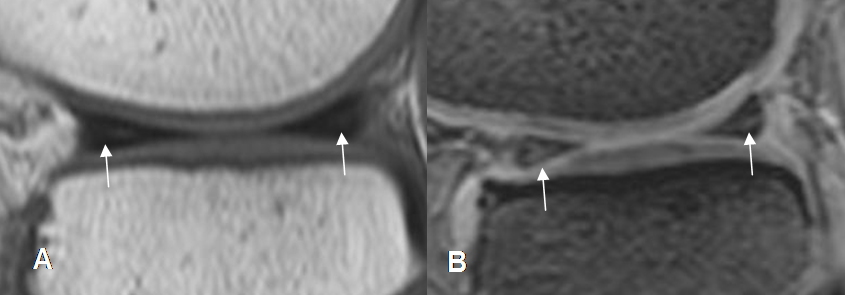

Fig 71. Ruptura meniscal horizontal.

A: RM sagital en T1 y B: RM sagital en STIR. Imagen en sentido horizontal que se comunica el borde libre y la superficie articular inferior, por ruptura meniscal.